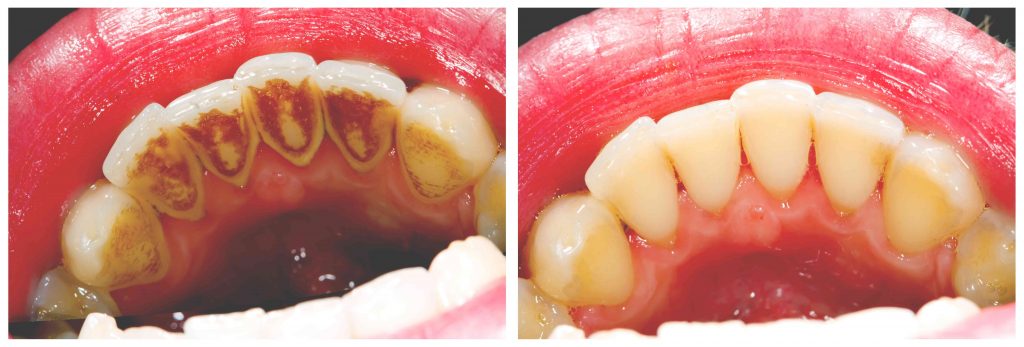

Very specific instruments are used to target each and every surface of the teeth to mechanically release mineral and bacteria above and below the gums. Only when this debris is completely removed can the gum disease reverse or stabilize. Although this falls under a ‘clean’, this procedure requires a high level of skill set, precision and clinical time. The care and technique used makes all the difference in terms of whether or not the gum disease is truly managed. A ‘quick clean’ will only remove stains you can see, but often make no difference to significant underlying gum disease.

It takes a dedicated team to tackle gum disease. As a part of modern dental care with a preventive approach to maximise the longevity of the teeth with as little restorative work as possible, more focus is given to the careful examination of teeth and the hygiene clean itself. For most adults it’s simply not possible (not in a good long term dental care sense) to carry out a combined examination and hygiene clean within 10 to 20 minutes. In order to manage gum disease, The Smile Team at Balwyn North dentists and oral health therapists work together to preserve your dental health for the long term through dedicating more time and care to this very important part of modern dental care and dental health.